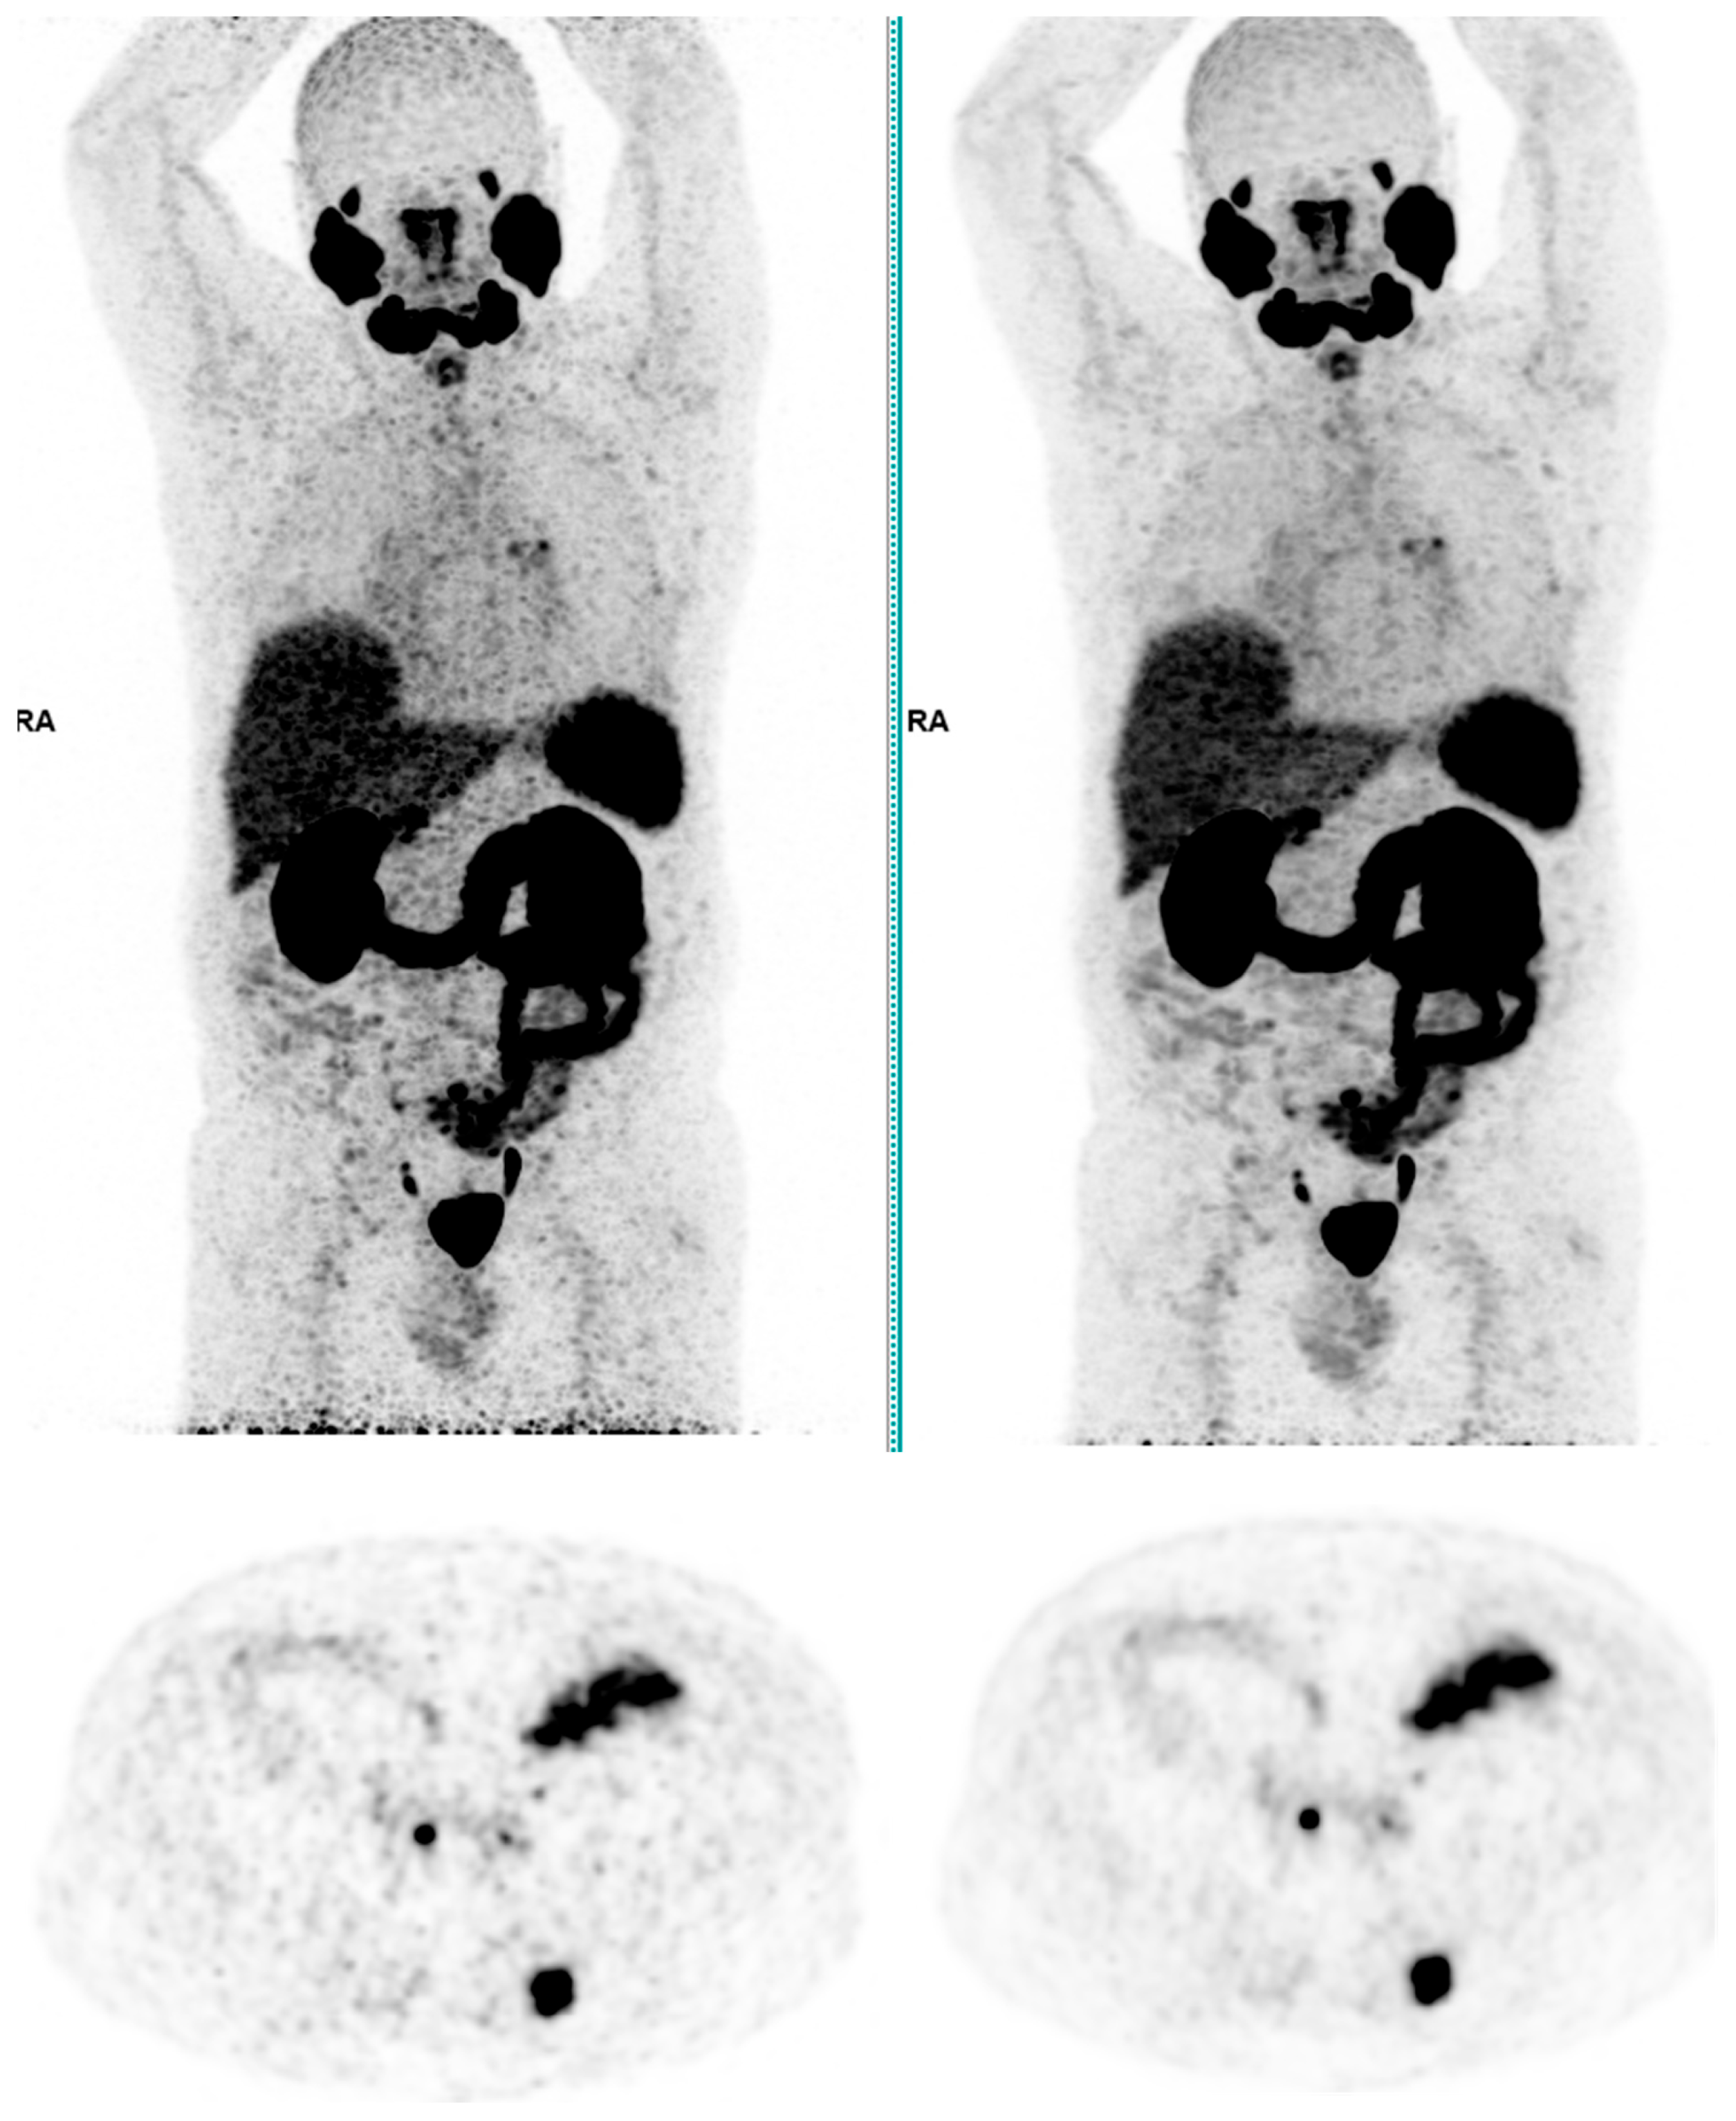

Across the three radiotracers, the AI-denoised images demonstrated a significantly improved performance in the visual analysis compared to conventional PET images. AI-denoised images were rated as interpretable (scores of 3–5) in all cases, compared to 65% for conventional images. Furthermore, an excellent image quality (score of 5) was achieved in 85% of all AI-denoised images, a significant improvement compared to the 50% in standard acquisitions. SubtlePET™ processing resulted in consistently lower noise levels, particularly for 18F-FDG scans, where 85% of images scored 4 or 5 for noise reduction compared to 60% in conventional scans. Lesion detectability was maintained or enhanced across all radiotracers, ensuring no compromise in the diagnostic accuracy. For 18F-FDOPA, a tracer with inherently lower signal-to-noise ratios, the AI algorithm improved the detection confidence by 25% compared to standard protocols. The visual comparison is illustrated through different MIP images and transaxial images (Figure 1, Figure 2, Figure 3 and Figure 4)

Figure 3. Total body 68Ga-PSMA-11 PET CT, MIP and transaxial images (left: without AI denoising; right: with AI denoising).